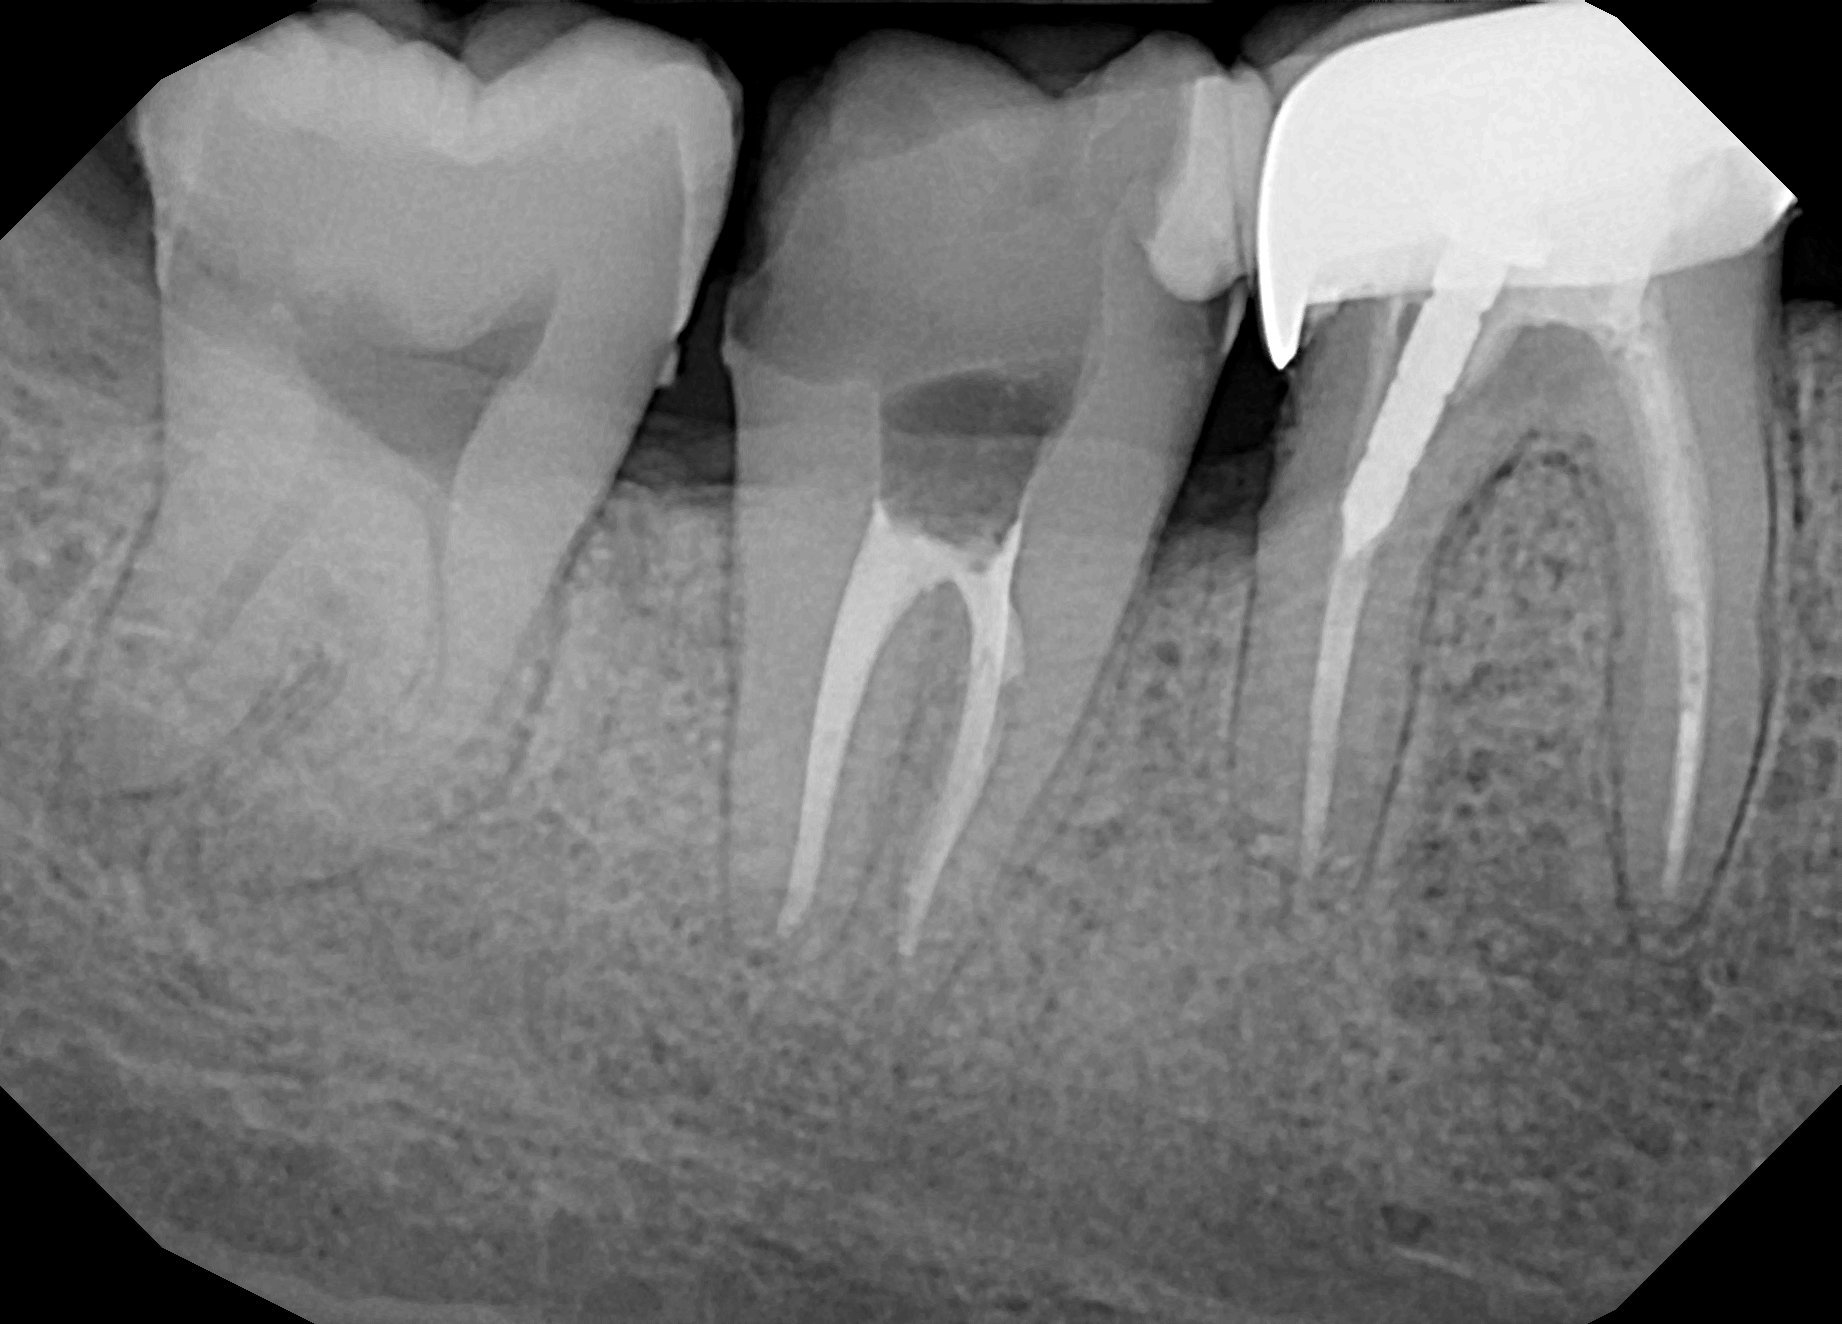

За да се запази мъдрец, той не трябва да боли, не трябва да създава проблеми, да може да се чисти лесно, да е функционален. Може и да има кариес. 7 зъб изглежда ок, изглежда машинно обработен, кореновото лечение се преценява с повече клинична информация, снимката е едната част. На въпросите Ви трябва са се отговори персонално след преглед. По снимка само аз не бих взимал решения.